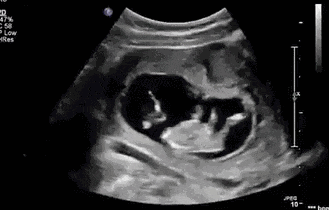

首先大家要知道,宝宝在妈妈肚子里是这样的~

是这样的....

这就是新生儿“鸟巢”式护理的依据~

新生儿“鸟巢式”护理是一种模仿子宫环境的护理方式。使胎儿在外部环境中仍然保持类似母体的卷曲姿势,为新生儿提供一个更加舒缓的过渡阶段,帮助新生儿逐渐消除脱离母体产生的紧张感,为新生儿提供安全感。